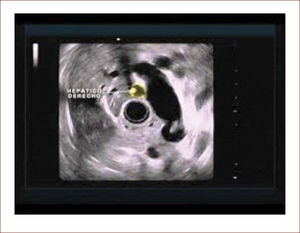

El 60% de las endosonografías remitidas a nuestro servicio, corresponde a pacientes con ictericia y sospecha de coledocolitiasis. En esta patología, la sensibilidad del EUS es mayor del 95%, como concluimos en un estudio próximo a publicarse, en el que los criterios de inclusión fueron pacientes con sospecha de cálculos del colédoco, EUS positivo para esta etiología y que nosotros mismos realizáramos la CPRE. Como se mencionó, en el 95% de los pacientes en los que el EUS mostró la presencia de cálculos en la vía biliar, coincidió con los hallazgos de la CPRE. Llamativamente, hubo 13 pacientes con MRI previa negativa para cálculos y que se remitieron por la persistencia de signos y síntomas sugestivos de cuadro litiásico, que solo pudieron ser demostrados con el EUS. El 5% restante de los pacientes diagnosticados por EUS como positivos para cálculos y sin correspondencia con los hallazgos de la CPRE, obedece posiblemente a la interpretación equívoca de imágenes o porque al momento de la CPRE, los cálculos ya hubieran salido espontáneamente a la luz intestinal. Figuras 3 y 4.

El paciente con ecografia y además imágenes que no mostraban compromiso de la vía biliar, ni de la vesícula. La resonancia magnética mostró vía biliar normal y descartó cálculos. El EUS mostró un cálculo pequeño menor de 3mm. Fue llevado a CPRE en forma temprana y el cuadro mejoró muchísimo. Hay que notar que la Resonancia a veces no detecta cálculos menores de 3mm.

Conclusión: El EUS en pancreatitis aguda tiene relevancia cuando se sospecha que la etiología es por cálculos biliares, pues su sensibilidad a este respecto es mucho mayor que la colangiorresonancia, detectando cálculos menores de 3mm. Por esta razón, como protocolo de nuestro servicio, los pacientes con pancreatitis, ictericia o colangitis, en los que otras imágenes diagnósticas no mostraron la posible causa del cuadro, se realizó una endosonografía bilio-pancreática y en caso de comprobar cálculos, lo hizo a una CPRE, en forma inmediata (solo basta cambiar el instrumento de trabajo). Con esta conducta, se optimizó la calidad del servicio prestado a nuestros pacientes, el tiempo de recuperación y de hospitalización se redujeron y el pronóstico mejoró.